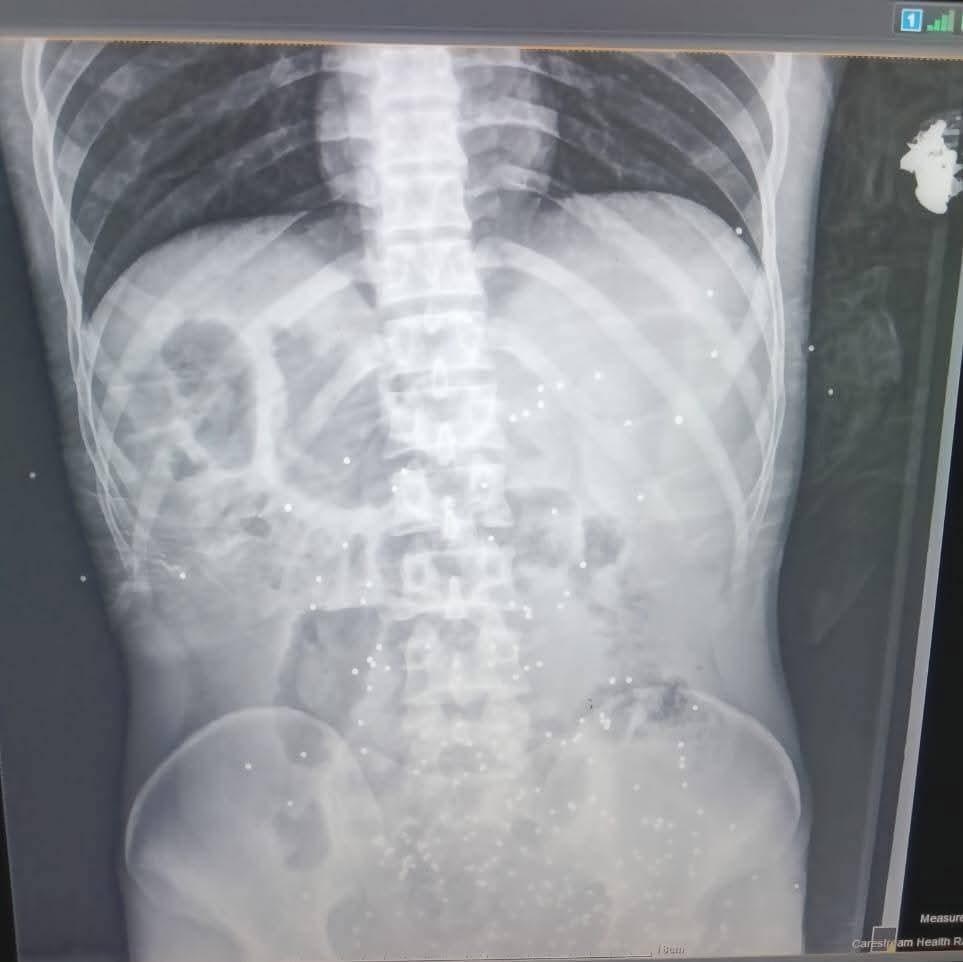

استقبلت طوارئ مستشفى ملوي التخصصي، جنوب محافظة المنيا شابًا في العقد الثالث من عمره، كان يعاني من حالة حرجة نتيجة تعرضه لحادث طلق ناري خرطوش بالبطن.

وأدى هذا الحادث إلى إصابات متعددة في منطقة البطن، مع اشتباه في إصابة الوريد المغذي للطرف السفلي، وكذلك اشتباه في إصابة المثانة ونزيف شديد من أماكن دخول الخرطوش.

وتم إدخال المريض إلى غرفة العمليات مباشرة، حيث قام الفريق الطبي بإجراء استكشاف للبطن، وتبين وجود نزيف داخلي وإصابات في الأمعاء ومساريقا البطن.. استمر العمل الجراحي لمدة خمس ساعات، حيث بذل أطباء الجراحة والتخدير جهودًا كبيرة للحفاظ على حياته.